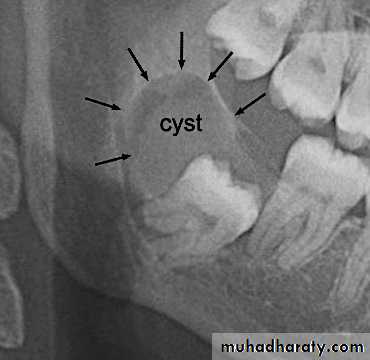

Removal of pathogenic bony conditions

( cyst, tumors)Cyst:…...enucleating or marsupialization